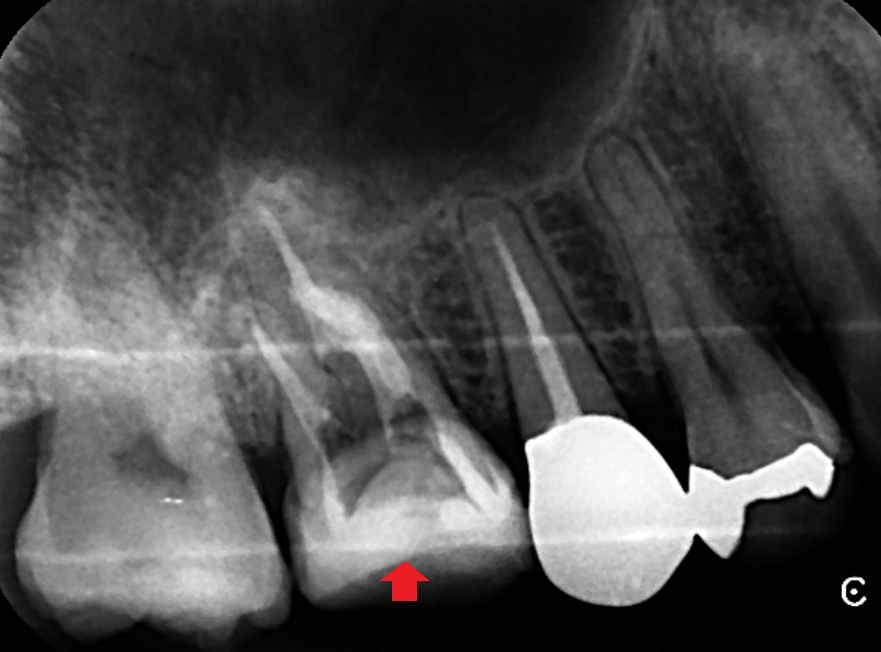

根管充填後のレントゲン写真です。精密根管治療により、近心頬側根の副根管とイスムスの清掃を徹底的にしました。